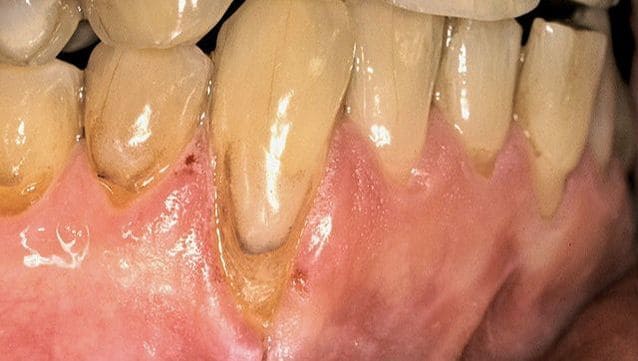

Before treatment Before